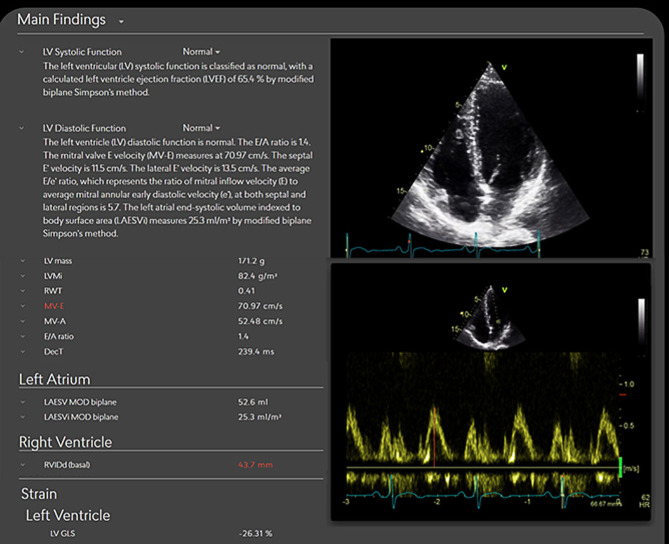

Transforming echocardiography with artificial intelligence.